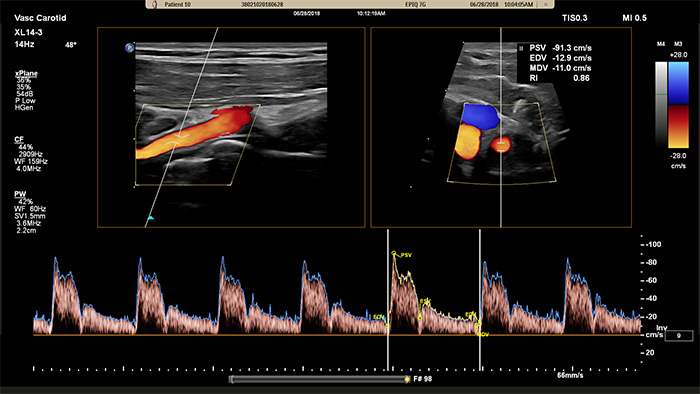

O XL14-3 xMATRIX também oferece capacidades do Doppler xPlane. O Doppler pulsado xPlane permite a colocação precisa do volume da amostra Doppler utilizando imagens de referência tanto longitudinais como transversais. O principal benefício: o Doppler xPlane reduz os erros de colocação do volume da amostra e proporciona maior reprodutibilidade e consistência ao obter amostras de estenose significativa.